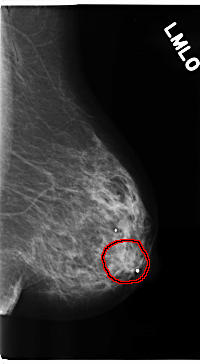

C_0206_1.LEFT_MLO

LEFT_MLO LINES 4728 PIXELS_PER_LINE 2592 BITS_PER_PIXEL 12 RESOLUTION 50 OVERLAY

FILE: C_0206_1.LEFT_MLO.OVERLAY

TOTAL_ABNORMALITIES 1

ABNORMALITY 1

LESION_TYPE MASS SHAPE LOBULATED MARGINS ILL_DEFINED

ASSESSMENT 4

SUBTLETY 3

PATHOLOGY MALIGNANT

TOTAL_OUTLINES 1

BOUNDARY